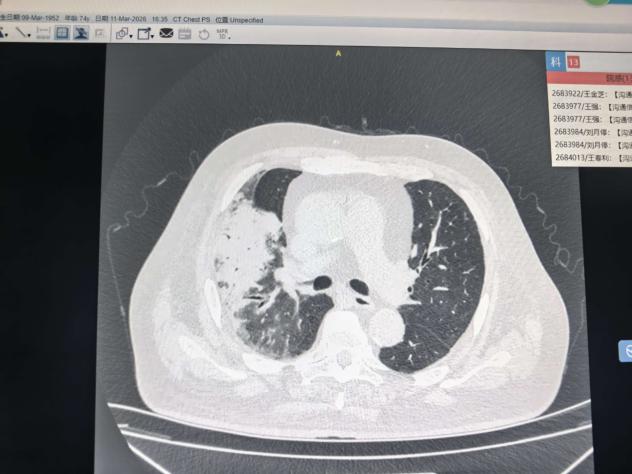

近日,我院RICU收治了一名70岁的重症肺炎患者孟大爷(化名)。孟大爷既往合并高血压、糖尿病、冠心病、肾功能不全等多种基础慢性病,此次严重的肺部感染进一步加重了机体负担。

随着各项检查结果陆续回报,患者的病情远比预想中更为复杂:BNP与心肌酶水平显著升高,动脉血pH值下降,PCT持续升高,提示感染控制不佳、心衰加重,同时合并高钾血症、I型呼吸衰竭、代谢性酸中毒等多种严重并发症,体内电解质及代谢紊乱问题突出。科主任王玉玲查看患者后当即指出:“患者因重症肺炎需使用高级别抗生素强效抗感染,但肾功能不全导致药物代谢能力极差,常规足量用药会加重肾脏负担;此外,输液治疗需严格把控出入量,警惕水负荷过重进一步加剧心衰。”